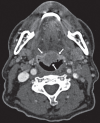

Paraneoplastic polyarthritis is an inflammatory arthritis, is usually seronegative, and has a temporal and pathophysiological relationship with an underlying malignancy. Although head and neck tumors may be a cause of paraneoplastic polyarthritis, its association with tongue carcinoma has not been previously reported. We present the case of a 69-year-old man who was a former smoker and presented with polyarthritis since 2 months in the wrists, proximal interphalangeal joints, knees, and elbows, with increased levels of acute-phase reactants; negativity for rheumatoid factor, anticitrullinated cyclic peptide antibody, and antinuclear antibody; and negative results for crystals and microorganisms in the synovial fluid. Cervical computed tomography and posterior rhinoscopy were performed, which detected an asymptomatic lesion on the base of the tongue, whose biopsy was compatible with nonkeratinizing squamous cell carcinoma. Polyarthritis did not respond to glucocorticoids at medium doses (oral prednisone 20 mg/day) but progressively resolved after the initiation of antineoplastic therapy.